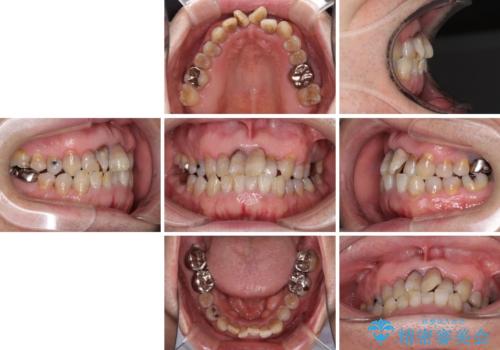

上顎の狭窄歯列 インビザラインによる拡大矯正

- 前歯の叢生と臼歯のクロスバイトを気にして来院された患者様です。

急速拡大装置による上顎の側方拡大を行い、その後はインビザラインより歯列を改善することとしました。

20代後半以降の男性は上顎骨の側方拡大処置の成功率が低く、今回も骨を拡大することができませんでした。

しかしながら、歯列を側方に拡大することができ、その後はインビザラインにて叢生を解消することができました。